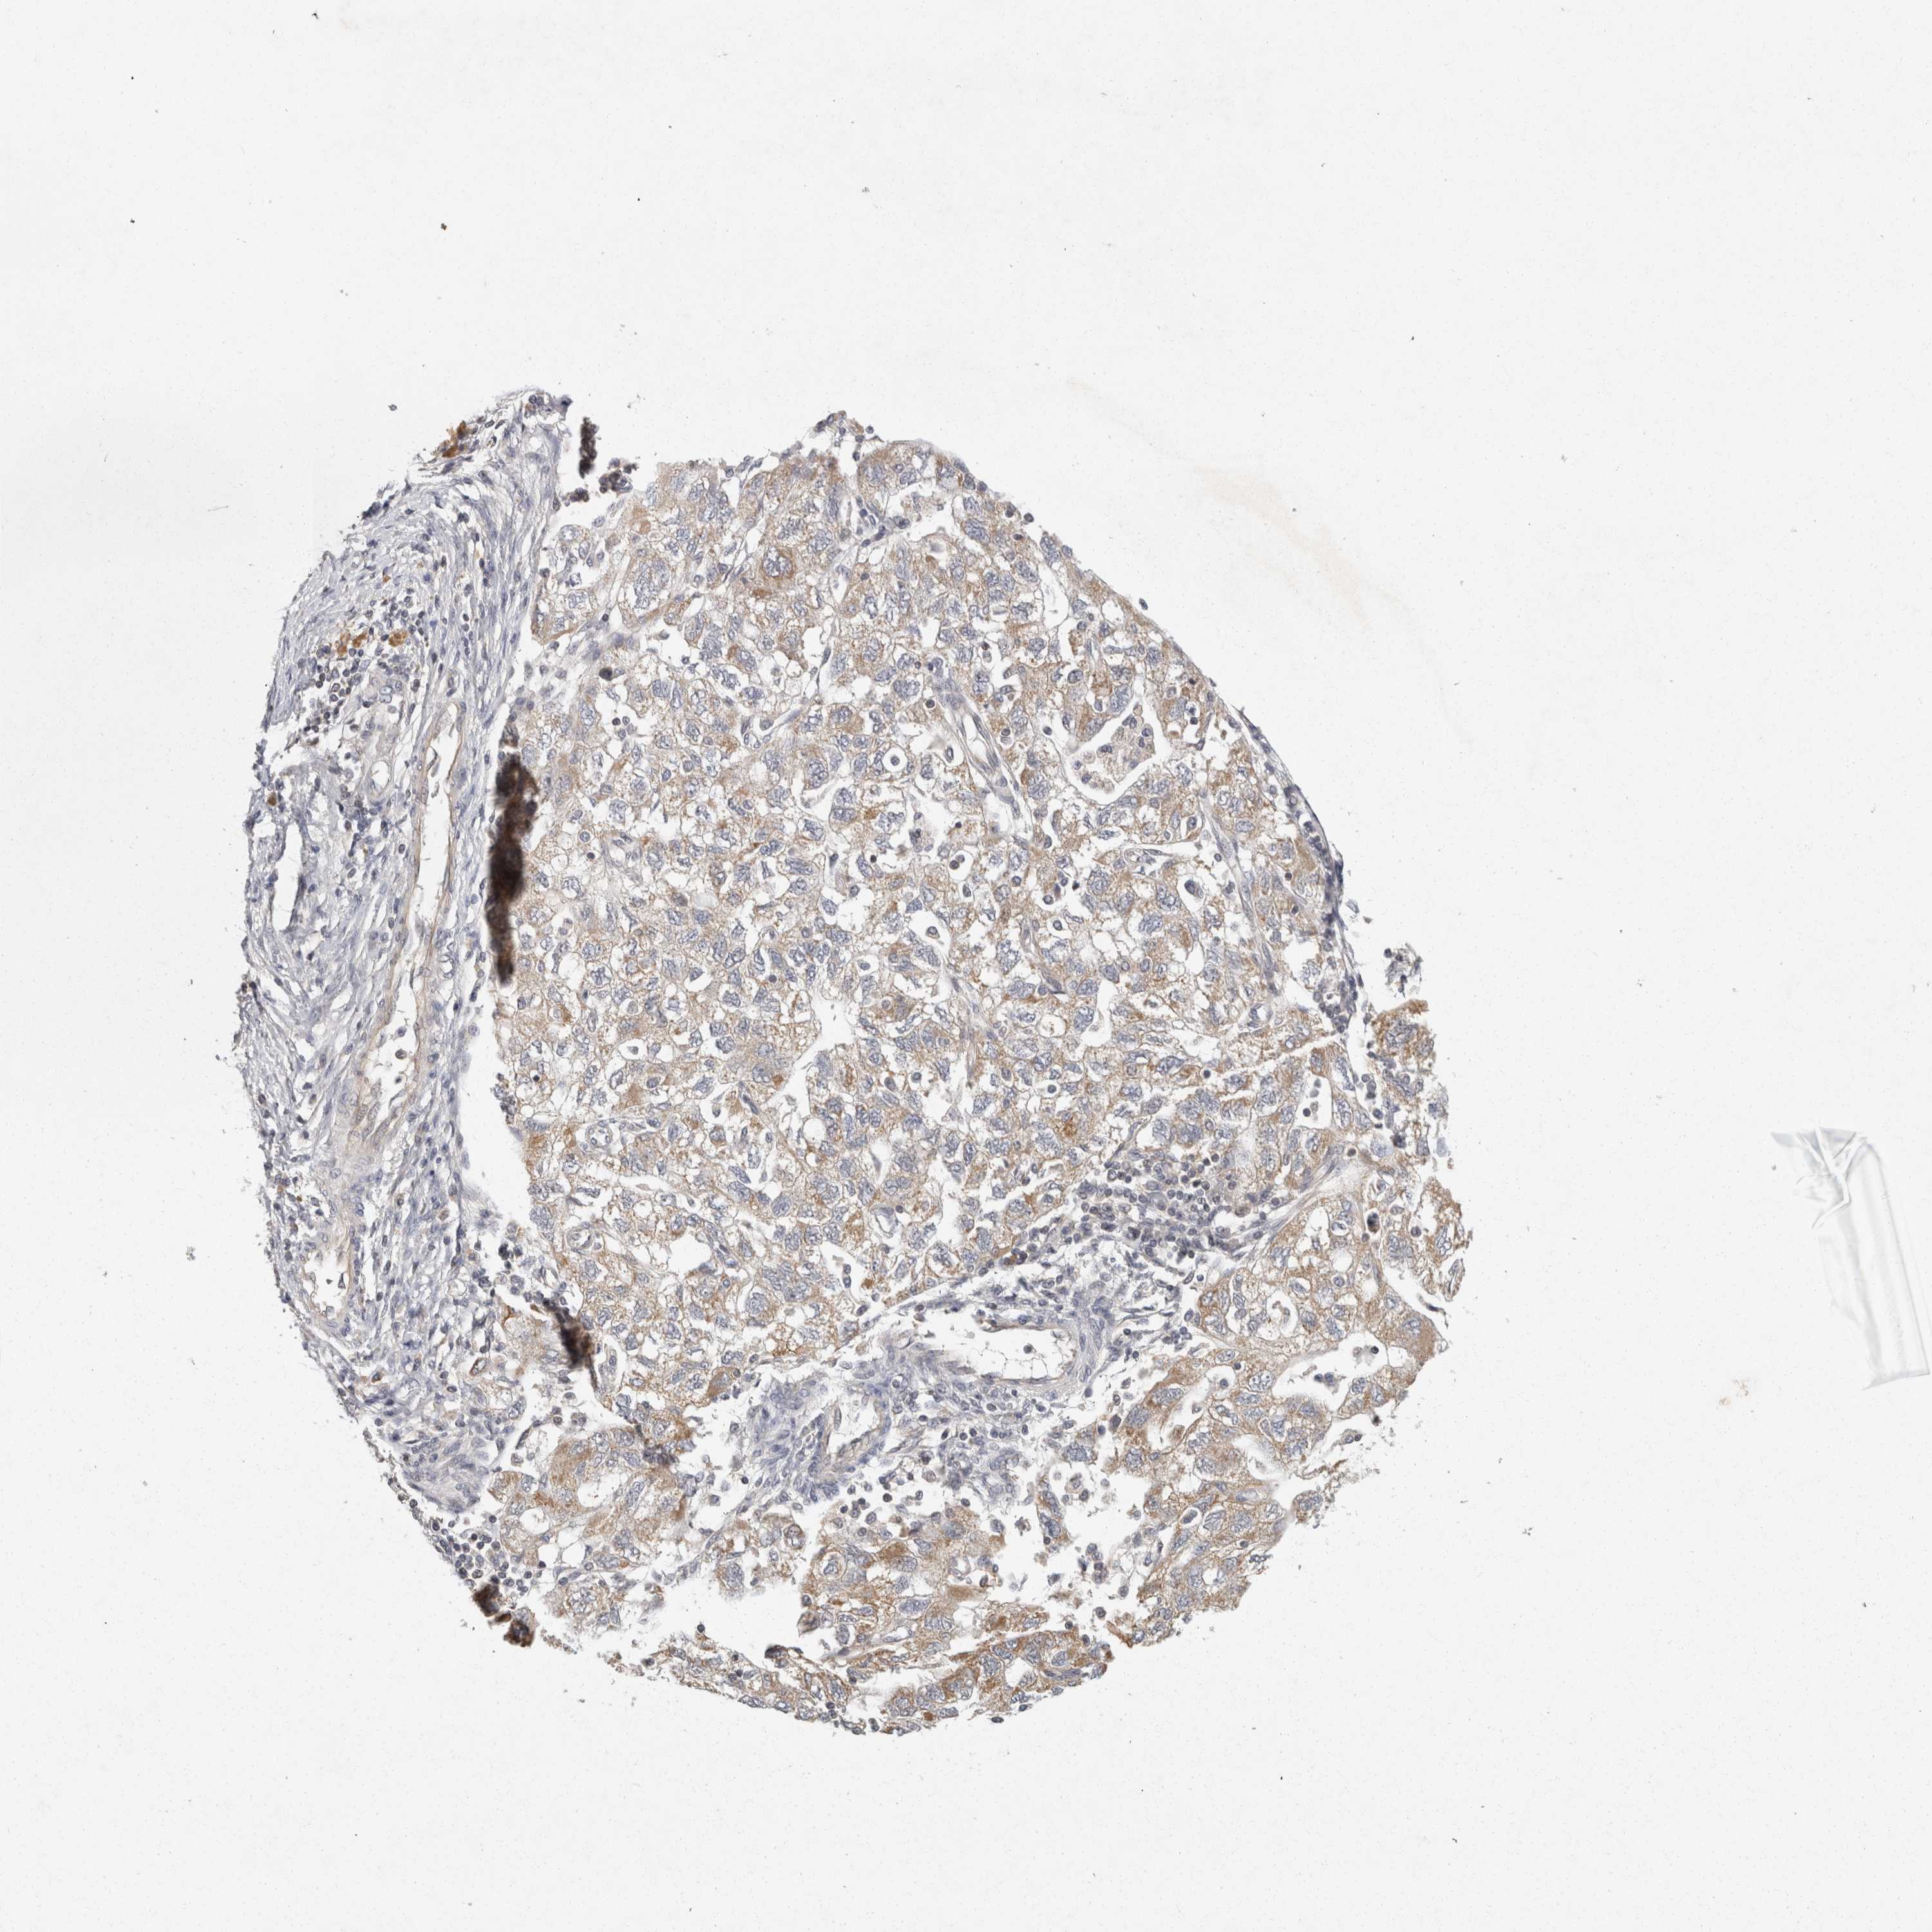

OVARIAN CANCER - Protein expressioni

A mouse-over function shows sample information and annotation data. Click on an image to view it in a full screen mode. Samples can be filtered based on level of antibody staining by selecting one or several of the following categories: high, medium, low and not detected. The assay and annotation is described here.

Note that samples used for immunohistochemistry by the Human Protein Atlas do not correspond to samples in the TCGA dataset.

Antibody stainingi

Antibody staining in the annotated cell types in the current human tissue is reported as not detected, low, medium, or high, based on conventional immunohistochemistry profiling in selected tissues. This score is based on the combination of the staining intensity and fraction of stained cells.

Each image is clickable and will lead to virtual microscopy that enables deeper exploration of all samples and also displays staining intensity scores, fraction scores and subcellular localization as well as patient and tissue information for each sample.

Antibody HPA025736

Antibody HPA025765

Antibody HPA025811

Antibody CAB021106

Cystadenocarcinoma, serous, NOS